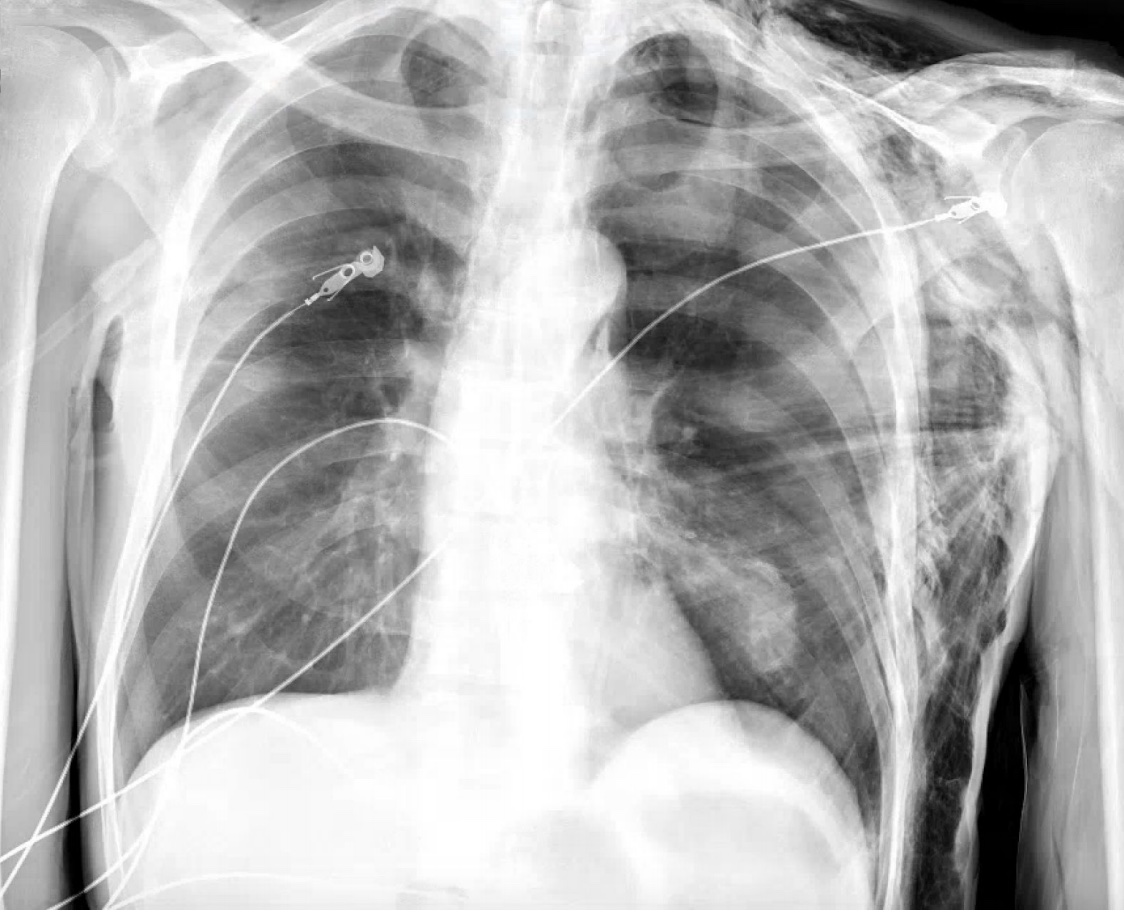

A 65 yo male presents with chest swelling gradually worsening over the past 2 hours. He has no history of trauma. His family reports that he had a bronchoscopy and video-assisted thorascopic surgery (VATS) 5 days ago. Patient is hemodynamically stable. He has palpable crepitus over chest wall extending into his neck and balck. A portable chest x-ray is shown. What's the diagnosis? Scroll down for answer.

Answer: Subcutaneous emphysema

Etiologies: Pneumothorax (spontaneous or traumatic), trauma (tracheobronchial injury, barotrauma), esophageal perforation/rupture, iotrogenic (from positive pressure ventilation, VATS, bronchoscopy), cocaine inhalation

Signs and symptoms: chest pain, dyspnea, soft tissue swelling, crepitus

Imaging: chest x-ray, CT scan

Management: assume underlying pneumothorax even if not obvious on x-ray, control pain, if possible avoid positive pressure ventilation (PPV), may require thoracostomy tube (especially if patient needs PPV) consultation with cardiothoracic surgery and interventional pulmonology with esophageal or tracheobronchial injury, may require bronchoscopy for further evaluation

Often resolves spontaneously over 2 weeks